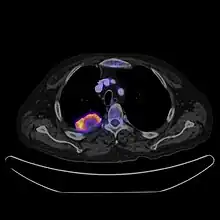

PET CT

Positron emission tomography–computed tomography is a hybrid CT modality which combines, in a single gantry, a positron emission tomography (PET) scanner and an X-ray computed tomography (CT) scanner, to acquire sequential images from both devices in the same session, which are combined into a single superposed (co-registered) image. Thus, functional imaging obtained by PET, which depicts the spatial distribution of metabolic or biochemical activity in the body can be more precisely aligned or correlated with anatomic imaging obtained by CT scanning.[24]

PET-CT gives both anatomical and functional details of an organ under examination and is helpful in detecting different type of cancers.[25][26]